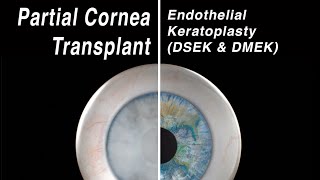

DMEK Surgery for Fuchs' Dystrophy Gives Dr. Coefield His Life Back Selective Cornea Transplant - Endothelial Keratoplasty (DMEK, DSEK)

Selective Cornea Transplant - Endothelial Keratoplasty (DMEK, DSEK) DMEK Corneal Transplant - Management of Fuch's Endothelial Dystrophy

DMEK Surgery for Fuchs' Dystrophy Gives Dr. Coefield His Life Back Selective Cornea Transplant - Endothelial Keratoplasty (DMEK, DSEK)

Selective Cornea Transplant - Endothelial Keratoplasty (DMEK, DSEK) DMEK Corneal Transplant - Management of Fuch's Endothelial Dystrophy